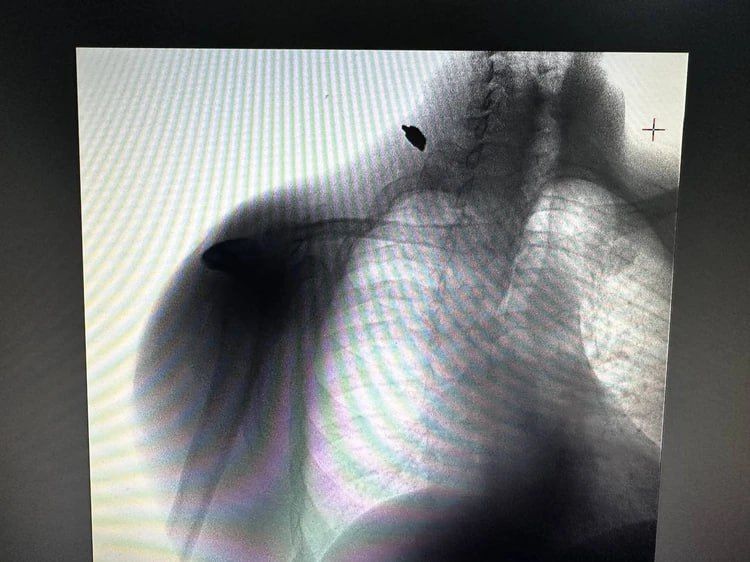

«Был дома, когда взорвался снаряд»: Медики спасли жителя Великой Лепетихи, попавшего под обстрел ВСУ

«Был дома, когда взорвался снаряд»: Медики спасли жителя Великой Лепетихи, попавшего под обстрел ВСУМедики спасли жителя Великой Лепетихи Херсонской области, который получил ранение под обстрелами ВСУ.Бригада скорой помощи в...